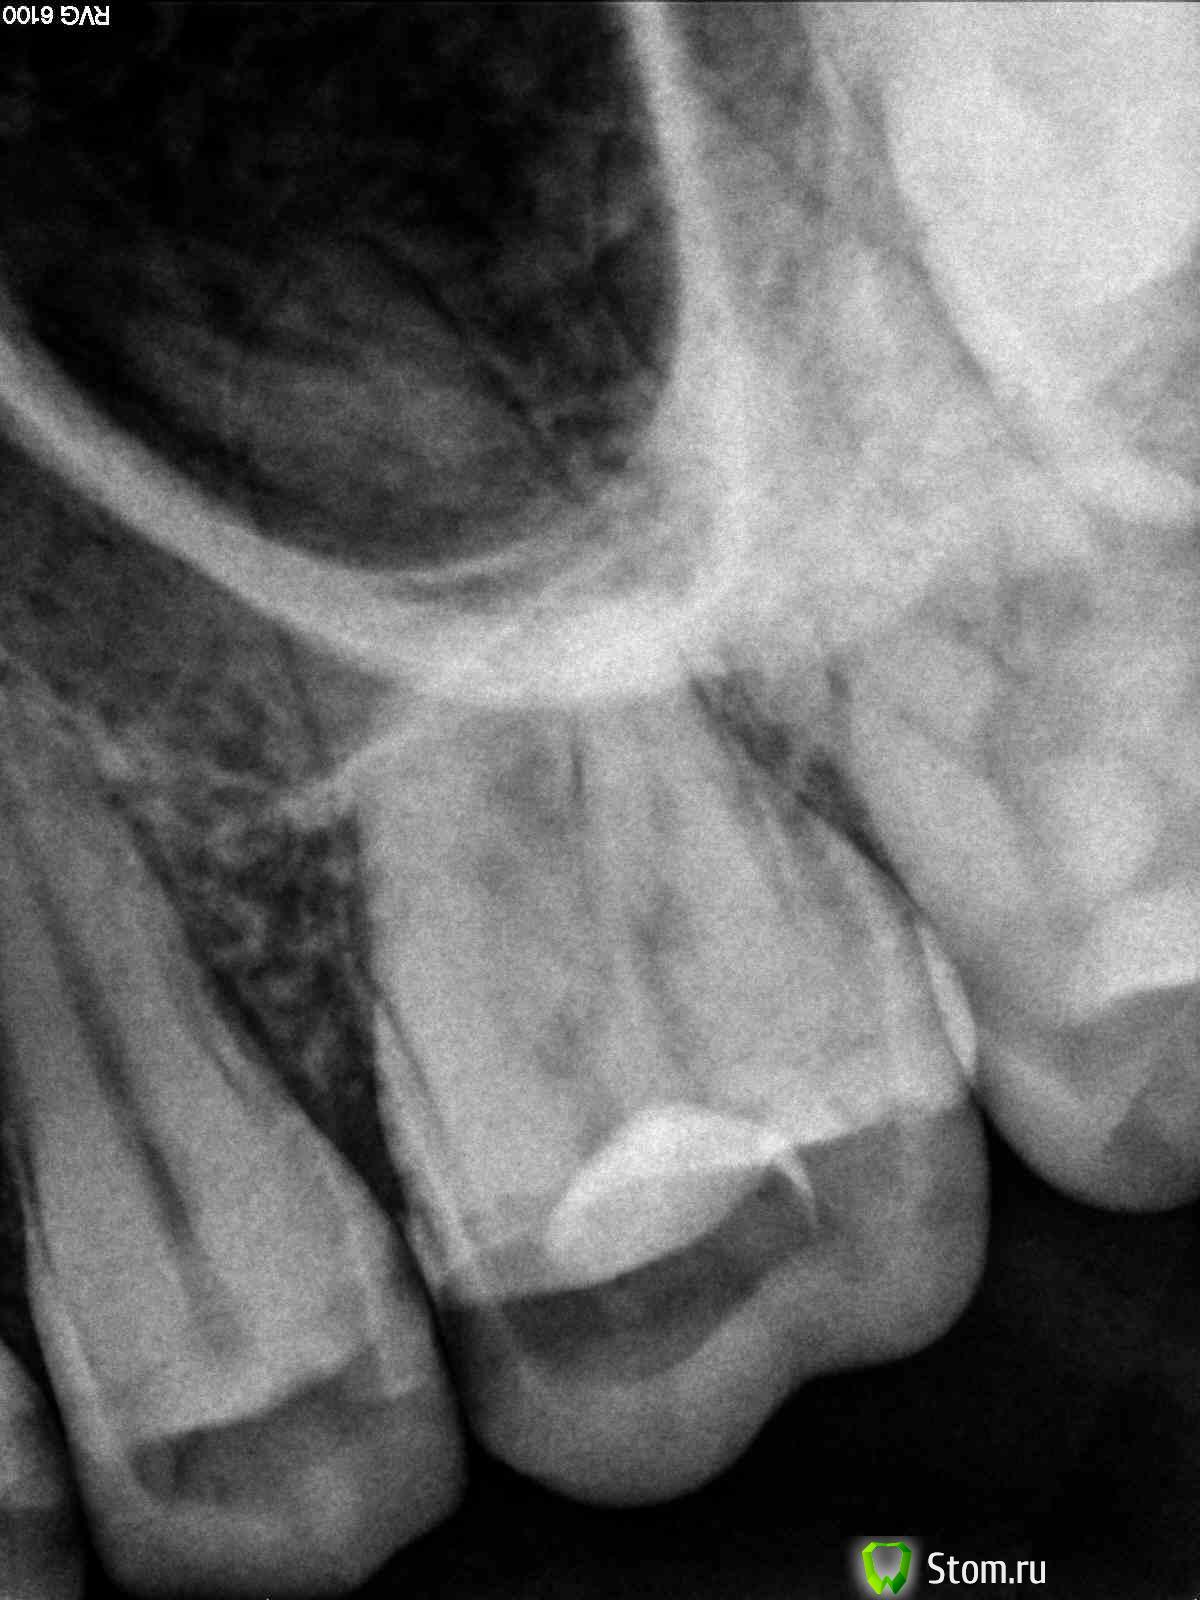

kurt Опубликовано 25 февраля, 2012 Автор Поделиться Опубликовано 25 февраля, 2012 (изменено) ув. juli63, снимки прилагаю ниже: на 1м, как понятно, это до лечения - удаления части нерва, на 2м это уже после установки постоянной пломбы - настоящее состояние зуба. ув. dmitrySH прав, что на снимке, если я не ошибаюсь, то эта поперечная трещина не видна. Изменено 25 февраля, 2012 пользователем kurt Ссылка на комментарий

juli63 Опубликовано 26 февраля, 2012 Поделиться Опубликовано 26 февраля, 2012 похоже, что перфорнули дно полости зуба(сделали дырку, где ее быть не должно), а нерв как был в зубе, так и есть. по снимку я за удаление. вас когда лечили-коффердам или раббердам использовали? Ссылка на комментарий

shishok Опубликовано 26 февраля, 2012 Поделиться Опубликовано 26 февраля, 2012 Корни(а их там 3)оставить нельзя-трещина проходит между ними.А по отдельности эти корни в функциональном плане бесполезны. Ссылка на комментарий